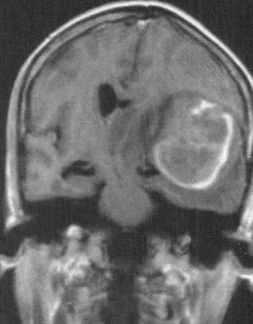

近期收治的两例患者中,一例为14岁青少年,因复发髓母细胞瘤合并出血入院,出血量约30ml;另一例为63岁长者,因突发意识障碍就医,CT提示颞枕叶出血量约70ml,伴有脑疝形成。神经外科团队在完善相关检查后,分别为两位患者开展急诊手术。术后患者意识状态逐步改善,神经功能恢复良好,复查影像学结果达到预期。